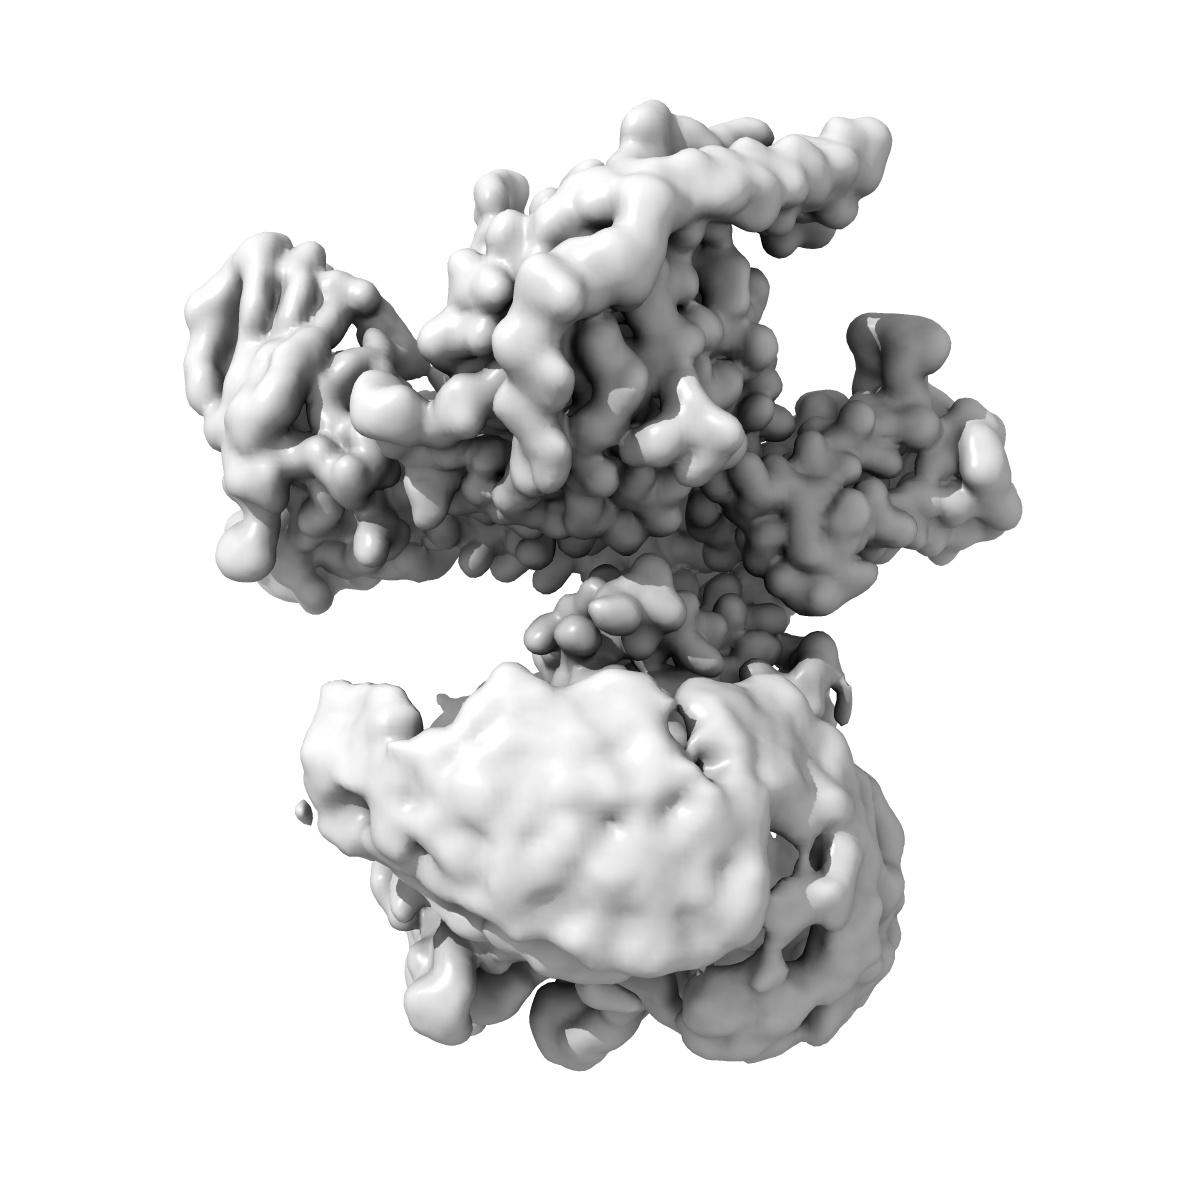

Cryo-EM structure of the C18:0 ceramide-bound FPR2-Gi complex

Single-particle3.2 Å

Sample: Cryo-EM structure of the C18:0 ceramide bound FPR2-Gi complex

Metabolic signaling of ceramides through the FPR2 receptor inhibits adipocyte thermogenesis.